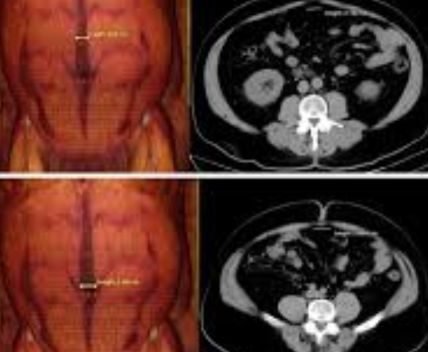

Ecografía

Mitos y Verdades

❌ Mito: “La ecografía usa radiación.”

✅ Verdad: Es un examen completamente seguro que utiliza ultrasonido.

❌ Mito: “Solo se usa durante el embarazo.”

✅ Verdad: Permite evaluar órganos, tejidos, músculos y detectar diversas enfermedades.

❌ Mito: “No necesita preparación.”

✅ Verdad: Algunos estudios requieren indicaciones previas para obtener resultados más precisos.